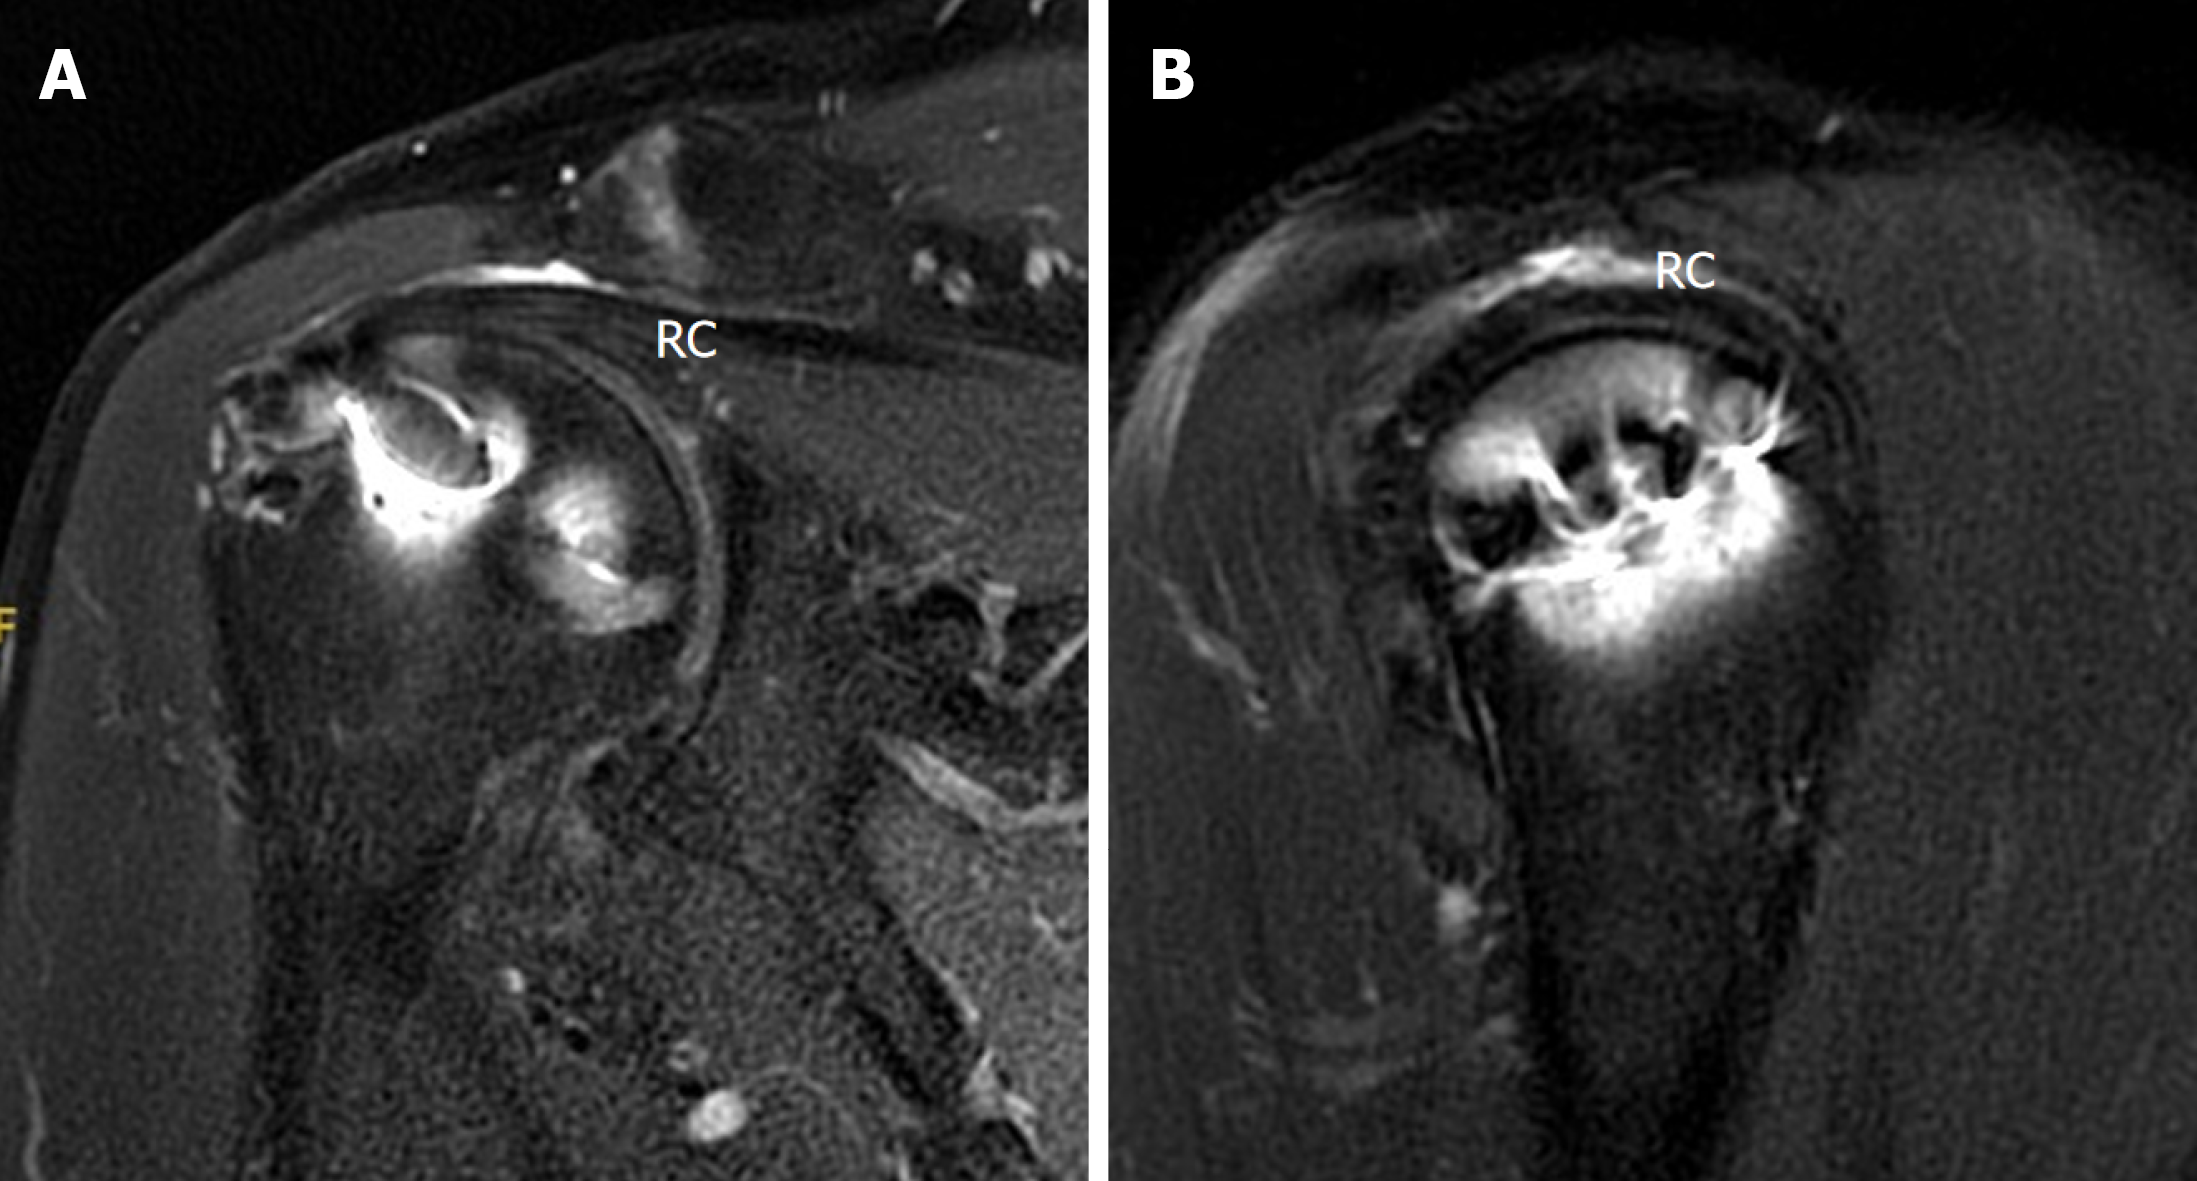

Figure 8 Magnetic resonance imaging at the 1-year follow-up revealed rotator cuff healing (Sugaya stage 1 or 2).

A: Coronal view; B: Sagittal view. RC: Rotator cuff.